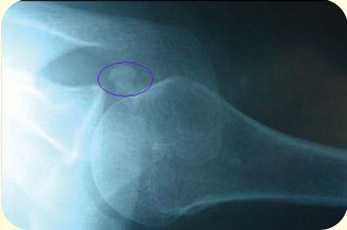

Диагноз ставиться после тщательного выяснения жалоб, анамнеза, осмотра и физикального исследования, анализа рентгенографических признаков кальциноза. Диагноз кальцифицирующего тендинита плеча подтверждается рентгенологически по наличию кальциноза сухожилия. Этот признак не всегда бывает легко обнаружить. Для его выявления выполняются снимки плечевого сустава в прямой проекции при нейтральном положении, а также наружной и внутренней ротации. На ранней стадии депозиты бывают плотными и хорошо определяются.

![]() | ![]() |

рентгенограммы плечевого сустава, кальцификаты обведены кружком